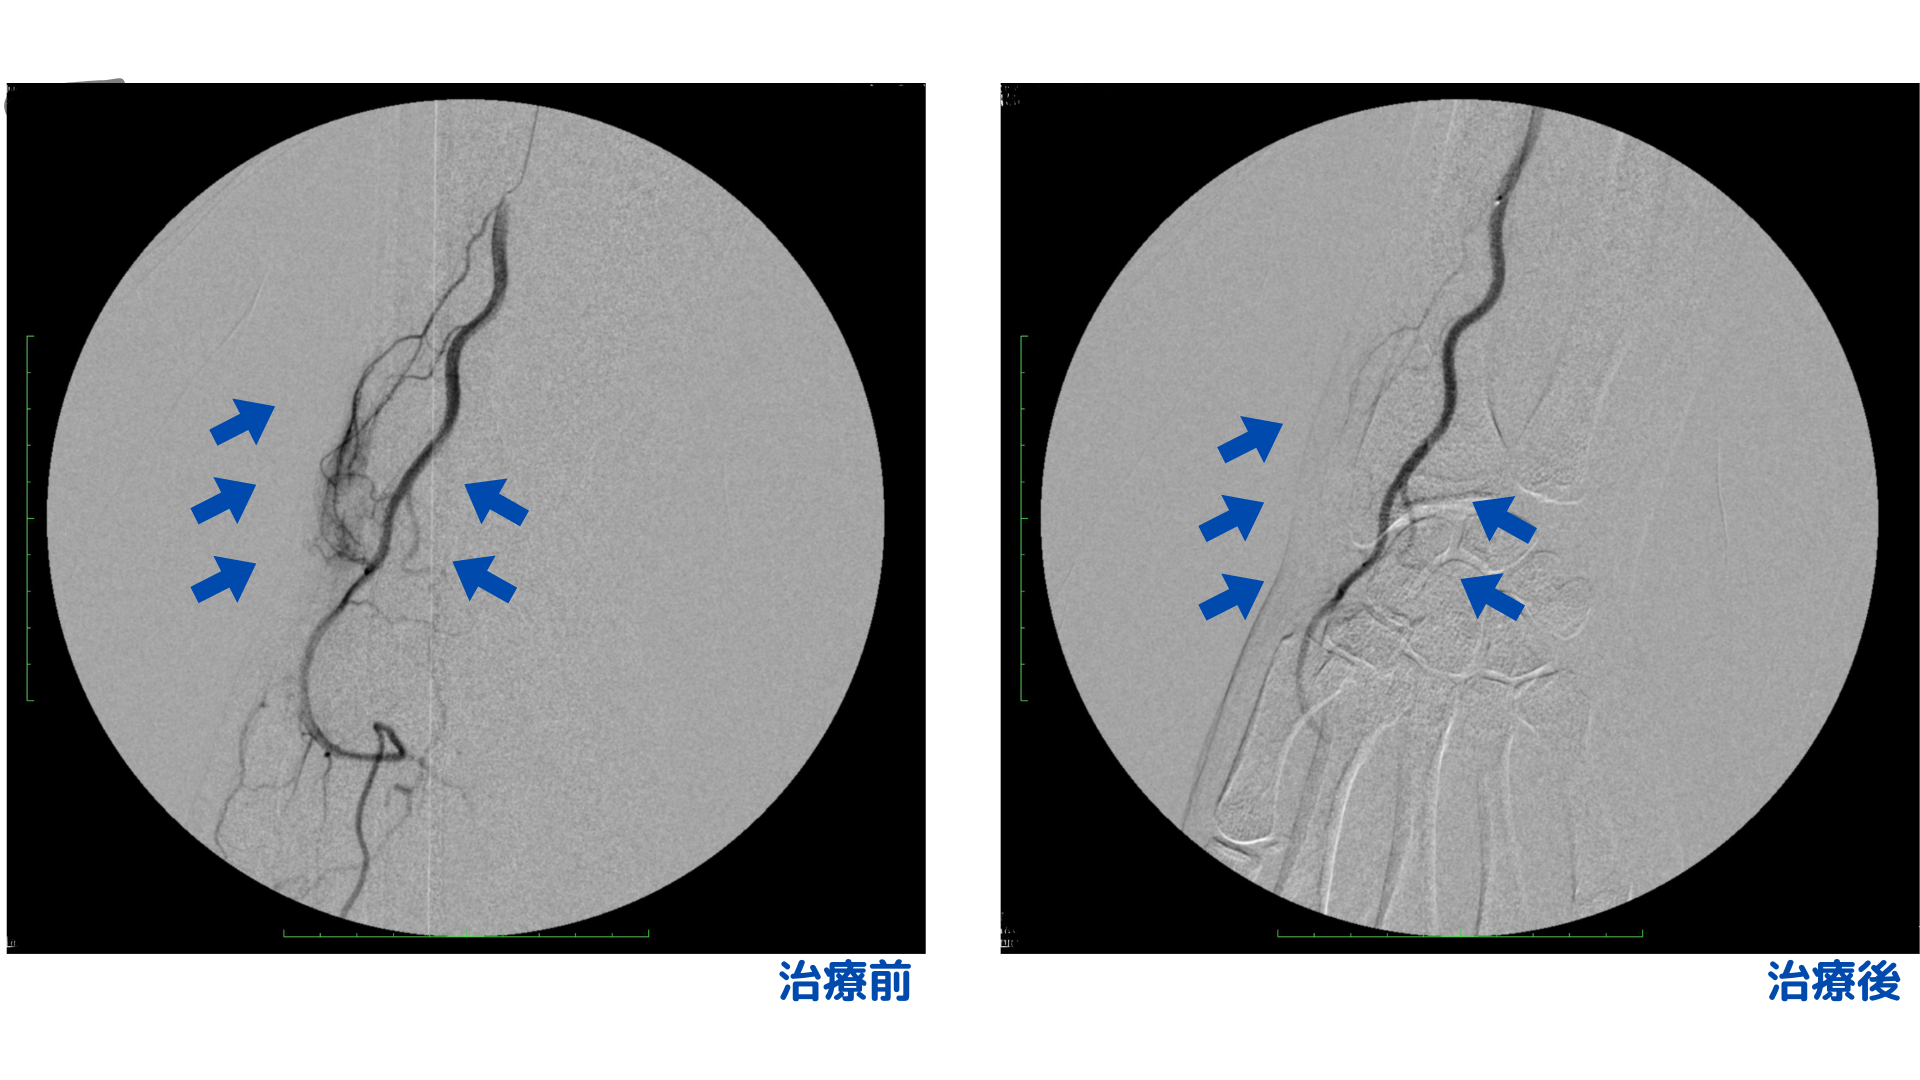

エコー検査にて、右手首および左手関節部に炎症と異常な血管(モヤモヤ血管)を確認しました。特に右手はドケルバン腱鞘炎が強く腫れも目立っていました。左右ともに痛みがあるものの、右側の痛みがより強く手を大きく動かそうとすると激しく痛みが増してしまうため、日常の動作にも大きな負担がかかっていました。

炎症が非常に強かったため、まずは両手に動注治療を行いました。しかし、初回治療後は痛みの改善がみられず、逆に痛みが強く出ることがありました。これは炎症が極めて強く、お薬が異常な血管のすみずみまで届ききっていない可能性が考えられたため、より直接的にアプローチできるカテーテル治療をご提案し治療しました。